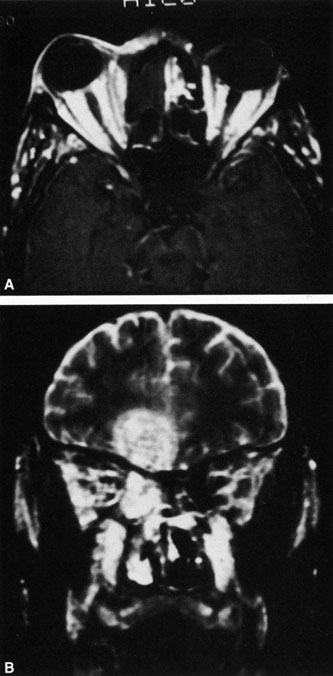

Magnetic resonance imaging (MRI) is purported to be more useful than CT in the diagnosis of preseptal cellulitis. It is less reliable at diagnosing the subtle signs of muscle enlargement and periscleritis and thus is not as useful in differentiating orbital cellulitis from other inflammatory orbital diseases.71 On MRI with gadolinium contrast, orbital cellulitis may show a smearing or linear streaking of the normal fat shadows on T2-weighted images. MRI is excellent for demonstrating localized fluid collections such as abscesses. It is not helpful in distinguishing a transudate from an exudate, because both appear liquid and are of low intensity on T1-weighted images and bright on T2-weighted images (Fig. 19).

Fig. 19. Magnetic resonance image of preseptal cellulitis with anterior abscess formation.

MRI is superior to CT in the diagnosis of cavernous sinus thrombosis. T2- and proton-weighted images show high signal luminal narrowing as well as absent flow or localized parenchymal infarcts (Fig. 20).72 Absent flow can be demonstrated as well in the superior ophthalmic vein in cases of carotid or cavernous sinus thrombosis.72 MRI with gadolinium can help define these abnormalities and can detect dural invasion.

Fig. 20. Cavernous sinus thrombosis. Axial T1 image shows cavernous carotid luminal narrowing on right and enlargement of right cavernous sinus. Note extensive sinus disease.